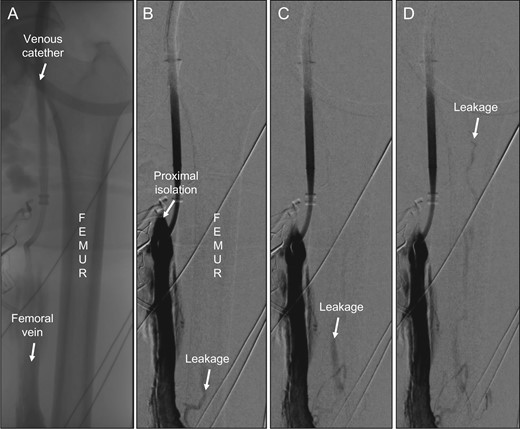

After re-application of Esmarch bands, there was still a high leakage rate. We performed a venography, which verified that there was no proximal femoral vein leakage. However, somewhat surprisingly, there was venous leakage through the femoral shaft that was clearly identified and recorded (Fig. 1A, 1B). A repeated venous angiogram confirmed a high venous flow through the nutrient medullary venous system of the femur (Fig. 1C) which caused the high leakage recorded by the precordial scintillator probe. The leakage made it impossible to continue with the perfusion. We decided to stop the perfusion, the patient never received any melphalan and she was afterwards referred for treatment with immunotherapy.

(A) Overview showing femur, the femoral vein and the venous catheter in place. (B) First venography showing the site of proximal isolation and leakage through the medullary vein in femur (arrow). (C) Successive image with proximal direction of leakage flow within the femur (arrow). (D) Continuous leakage through bone marrow up to femoral head (arrow).